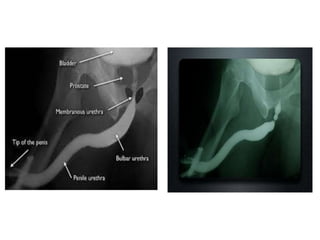

This document discusses the considerations and precautions for retrograde urethrography (RGU), noting that local anesthetic may cause issues such as mucosal edema. It highlights the need for antibiotic coverage due to potential complications like extravasation during contrast injection, and touches upon the role of cystography in pelvic fractures, indicating it can often be safely omitted. Additionally, it reports on complications related to urinary tract infections and reactions to contrast media, offering recommendations for patient management.